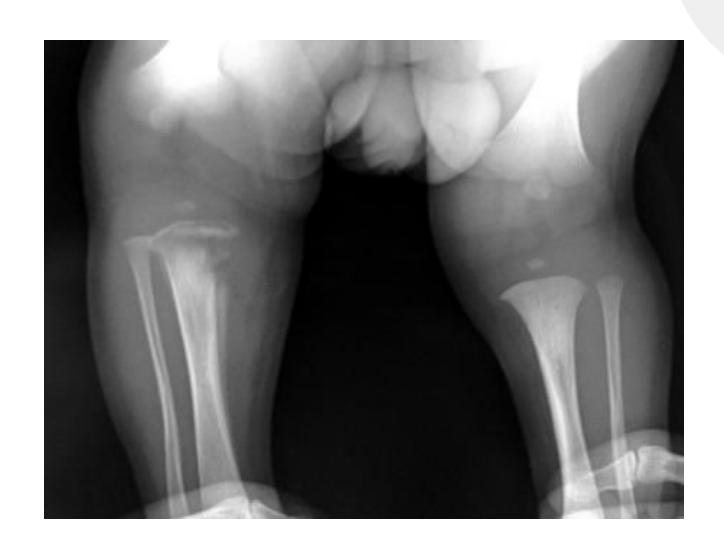

Rickets

Radiological Features

What are the characteristic x-ray findings in rickets?

- Widening of the epiphyseal plate

- Cupping of the metaphysis

- Irregular metaphyseal ends

- Widened physis

Pediatric Case Study

A 5-year-old boy was brought to the clinic because of a progressively increasing deformity in his left leg for 6 months.

What are the abnormal x-ray findings?

- Widening of epiphyseal plate

- Cupping of metaphysis

How will you treat the underlying cause?

- Vitamin D supplementation